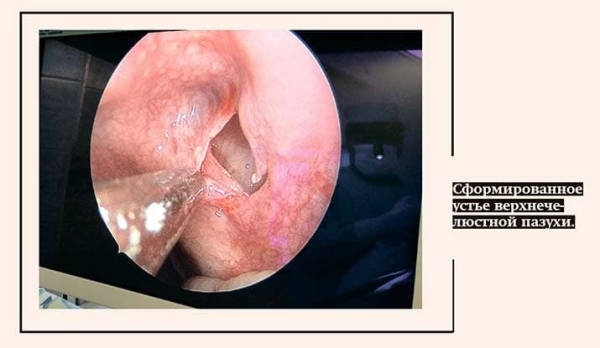

Эндоскопическая операция, как говорит специалист, весьма малотравматична (всего несколько миллиметров). Прооперированная пазуха тут же начинает функционировать без каких-либо проблем в дальнейшем.

Эндоскопическая хирургия носа, пазух, — это моя любимая тема. Опыт, а его немало у меня и моих коллег, позволяет выполнить чисто хирургическую работу за 3–5 минут. Это, конечно, если ничто не мешает, пациент стабилен, нет кровотечения, патологических изменений. Бывает, что обнаруживаем какие-то другие проблемы, о которых, впрочем, узнаем обычно, еще глядя на результаты КТ.